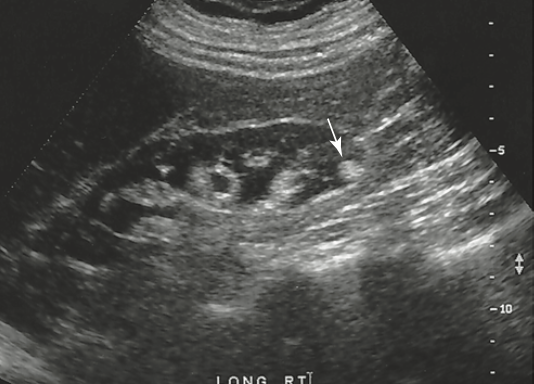

which of the following vascular structures does the arrow identify

right renal artery